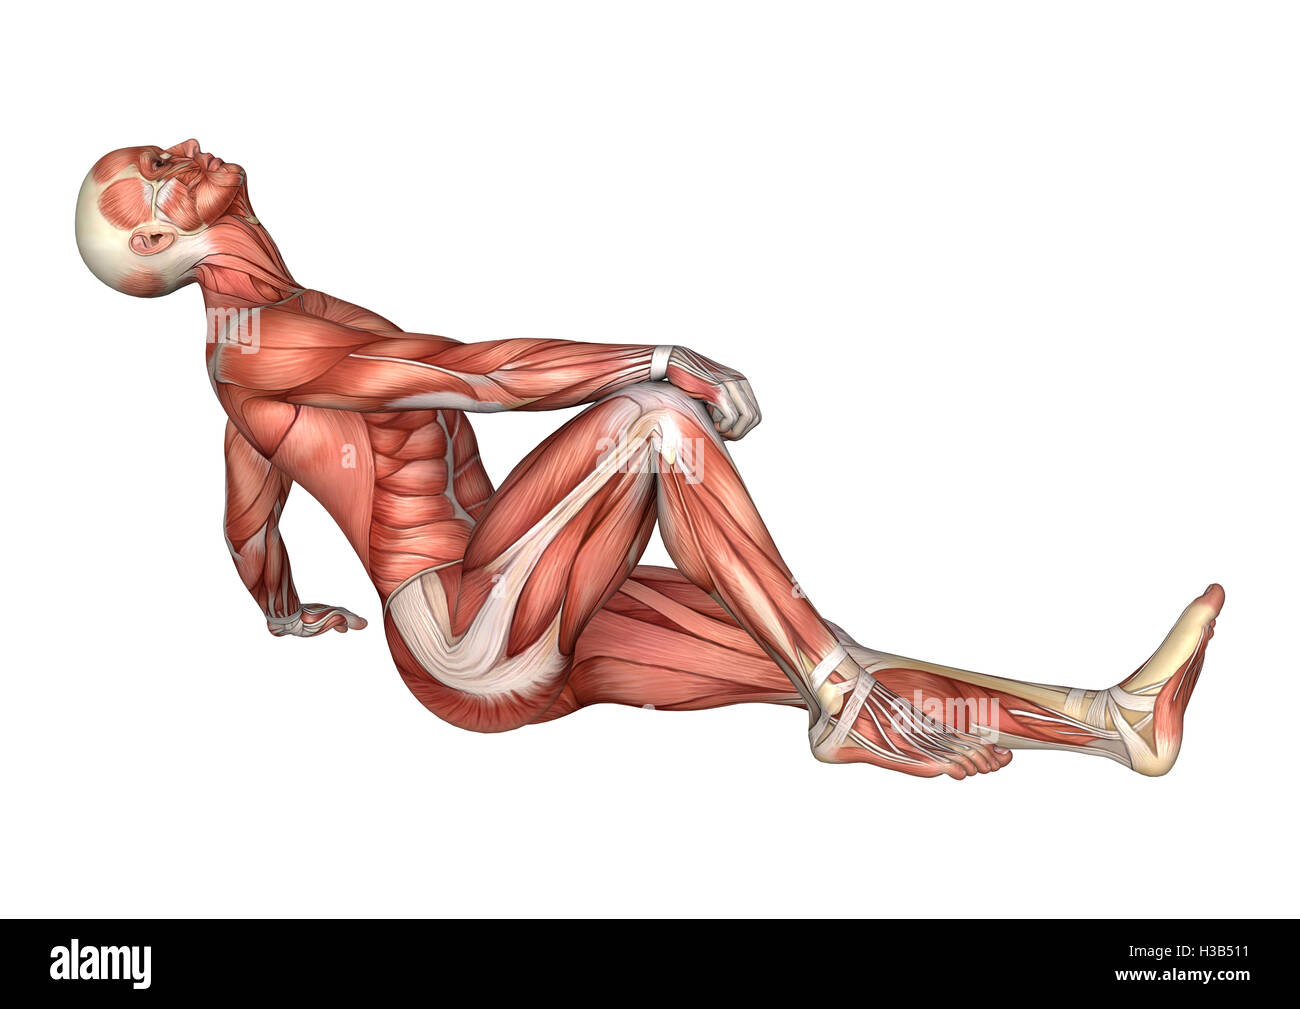

RFH3B511–3D-Rendering einer männlichen Anatomie-Figur mit Muskeln Karte isolierten auf weißen Hintergrund

RFH3B545–3D-Rendering einer männlichen Anatomie-Figur mit Muskeln Karte isolierten auf weißen Hintergrund